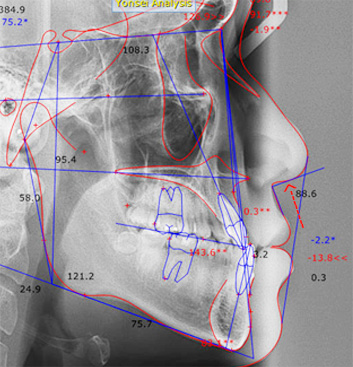

주걱턱으로 앞니가 서로 거꾸로 물리고 어금니가 제대로 물리지 않는 남환, 타 병원에서 양악 수술 진단을 받고 내원하셨습니다.

고운미소에서 교정용 미니스크류를 이용하여 아래 치열은 후방이동, 위 치열은 전방으로 이동하는 치료를 진행하였습니다.

위턱에 비해 아래턱이 크고 전방에 위치, 우측으로 변위된 비대칭을 보입니다.